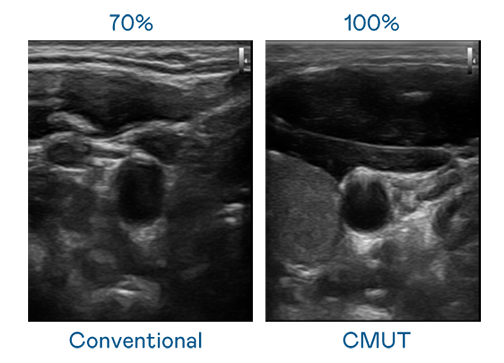

CMUT 技術是一種用電容式微機電元件來產生超音波訊號的技術。與傳統 PZT 壓電式技術相比,CMUT 頻寬增加 30%,更寬頻的超音波訊號讓影像解析度大幅提升,是實現高影像品質醫療超音波掃描、促進精準醫療發展的關鍵技術。

超音波影像的解析度高低,首先取決於探頭能發出的訊號頻寬。DB真人旗舰 CMUT 可提供高清晰的超音波訊號,提供高頻寬、高靈敏度、影像紋理細節更高的超音波影像,協助醫護人員縮短影像判讀時間及利用精準的醫療影像進行診斷。